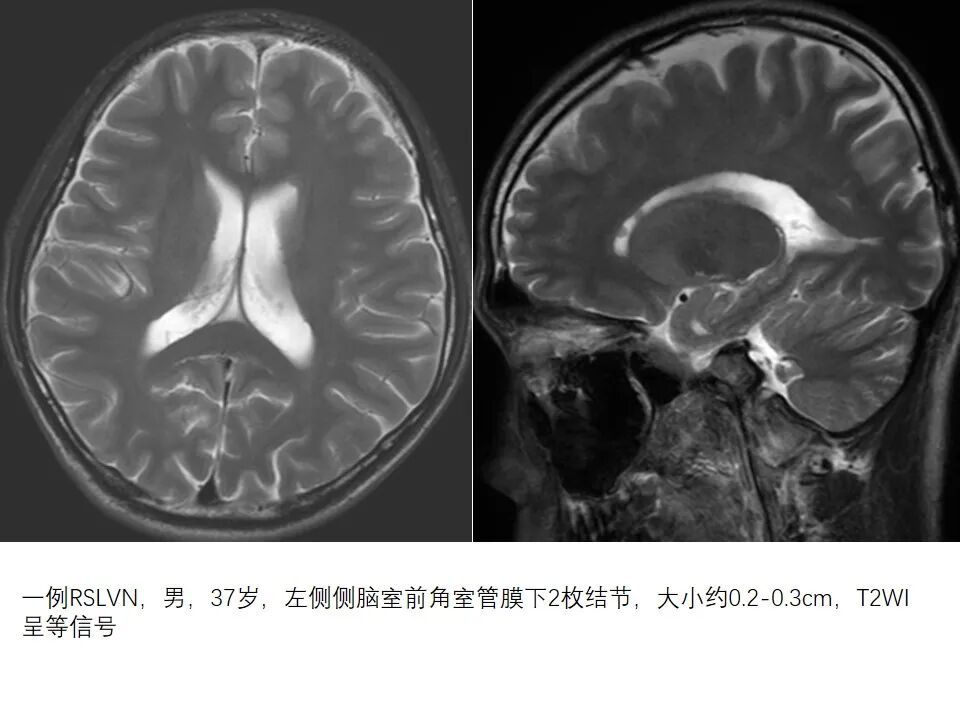

一例RSLVN,男,37岁,左侧侧脑室前角室管膜下2枚结节,大小约0.2-0.3cm,T2WI呈等信号